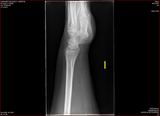

W22 Pols Gé 17-03-2011

17-03-2011 Geetje